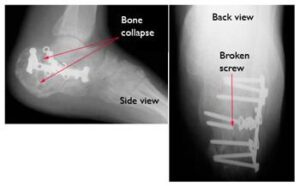

- If surgery has been performed, screws may loosen or break, and the bone could collapse.

- While the initial weight-bearing attempt may seem uneventful, continued pressure on an unhealed bone can lead to hardware failure and delayed recovery.

Six months after surgery, this patient's hardware has failed. Several screws have broken and the calcaneus has collapsed. This patient required major reconstruction, and today walks with a limp and has little motion in the foot.